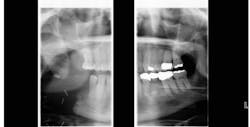

Thankfully, this time surgery was a success. The fistula is gone, and there have been no new ulcerated lesions to date (figure 3).